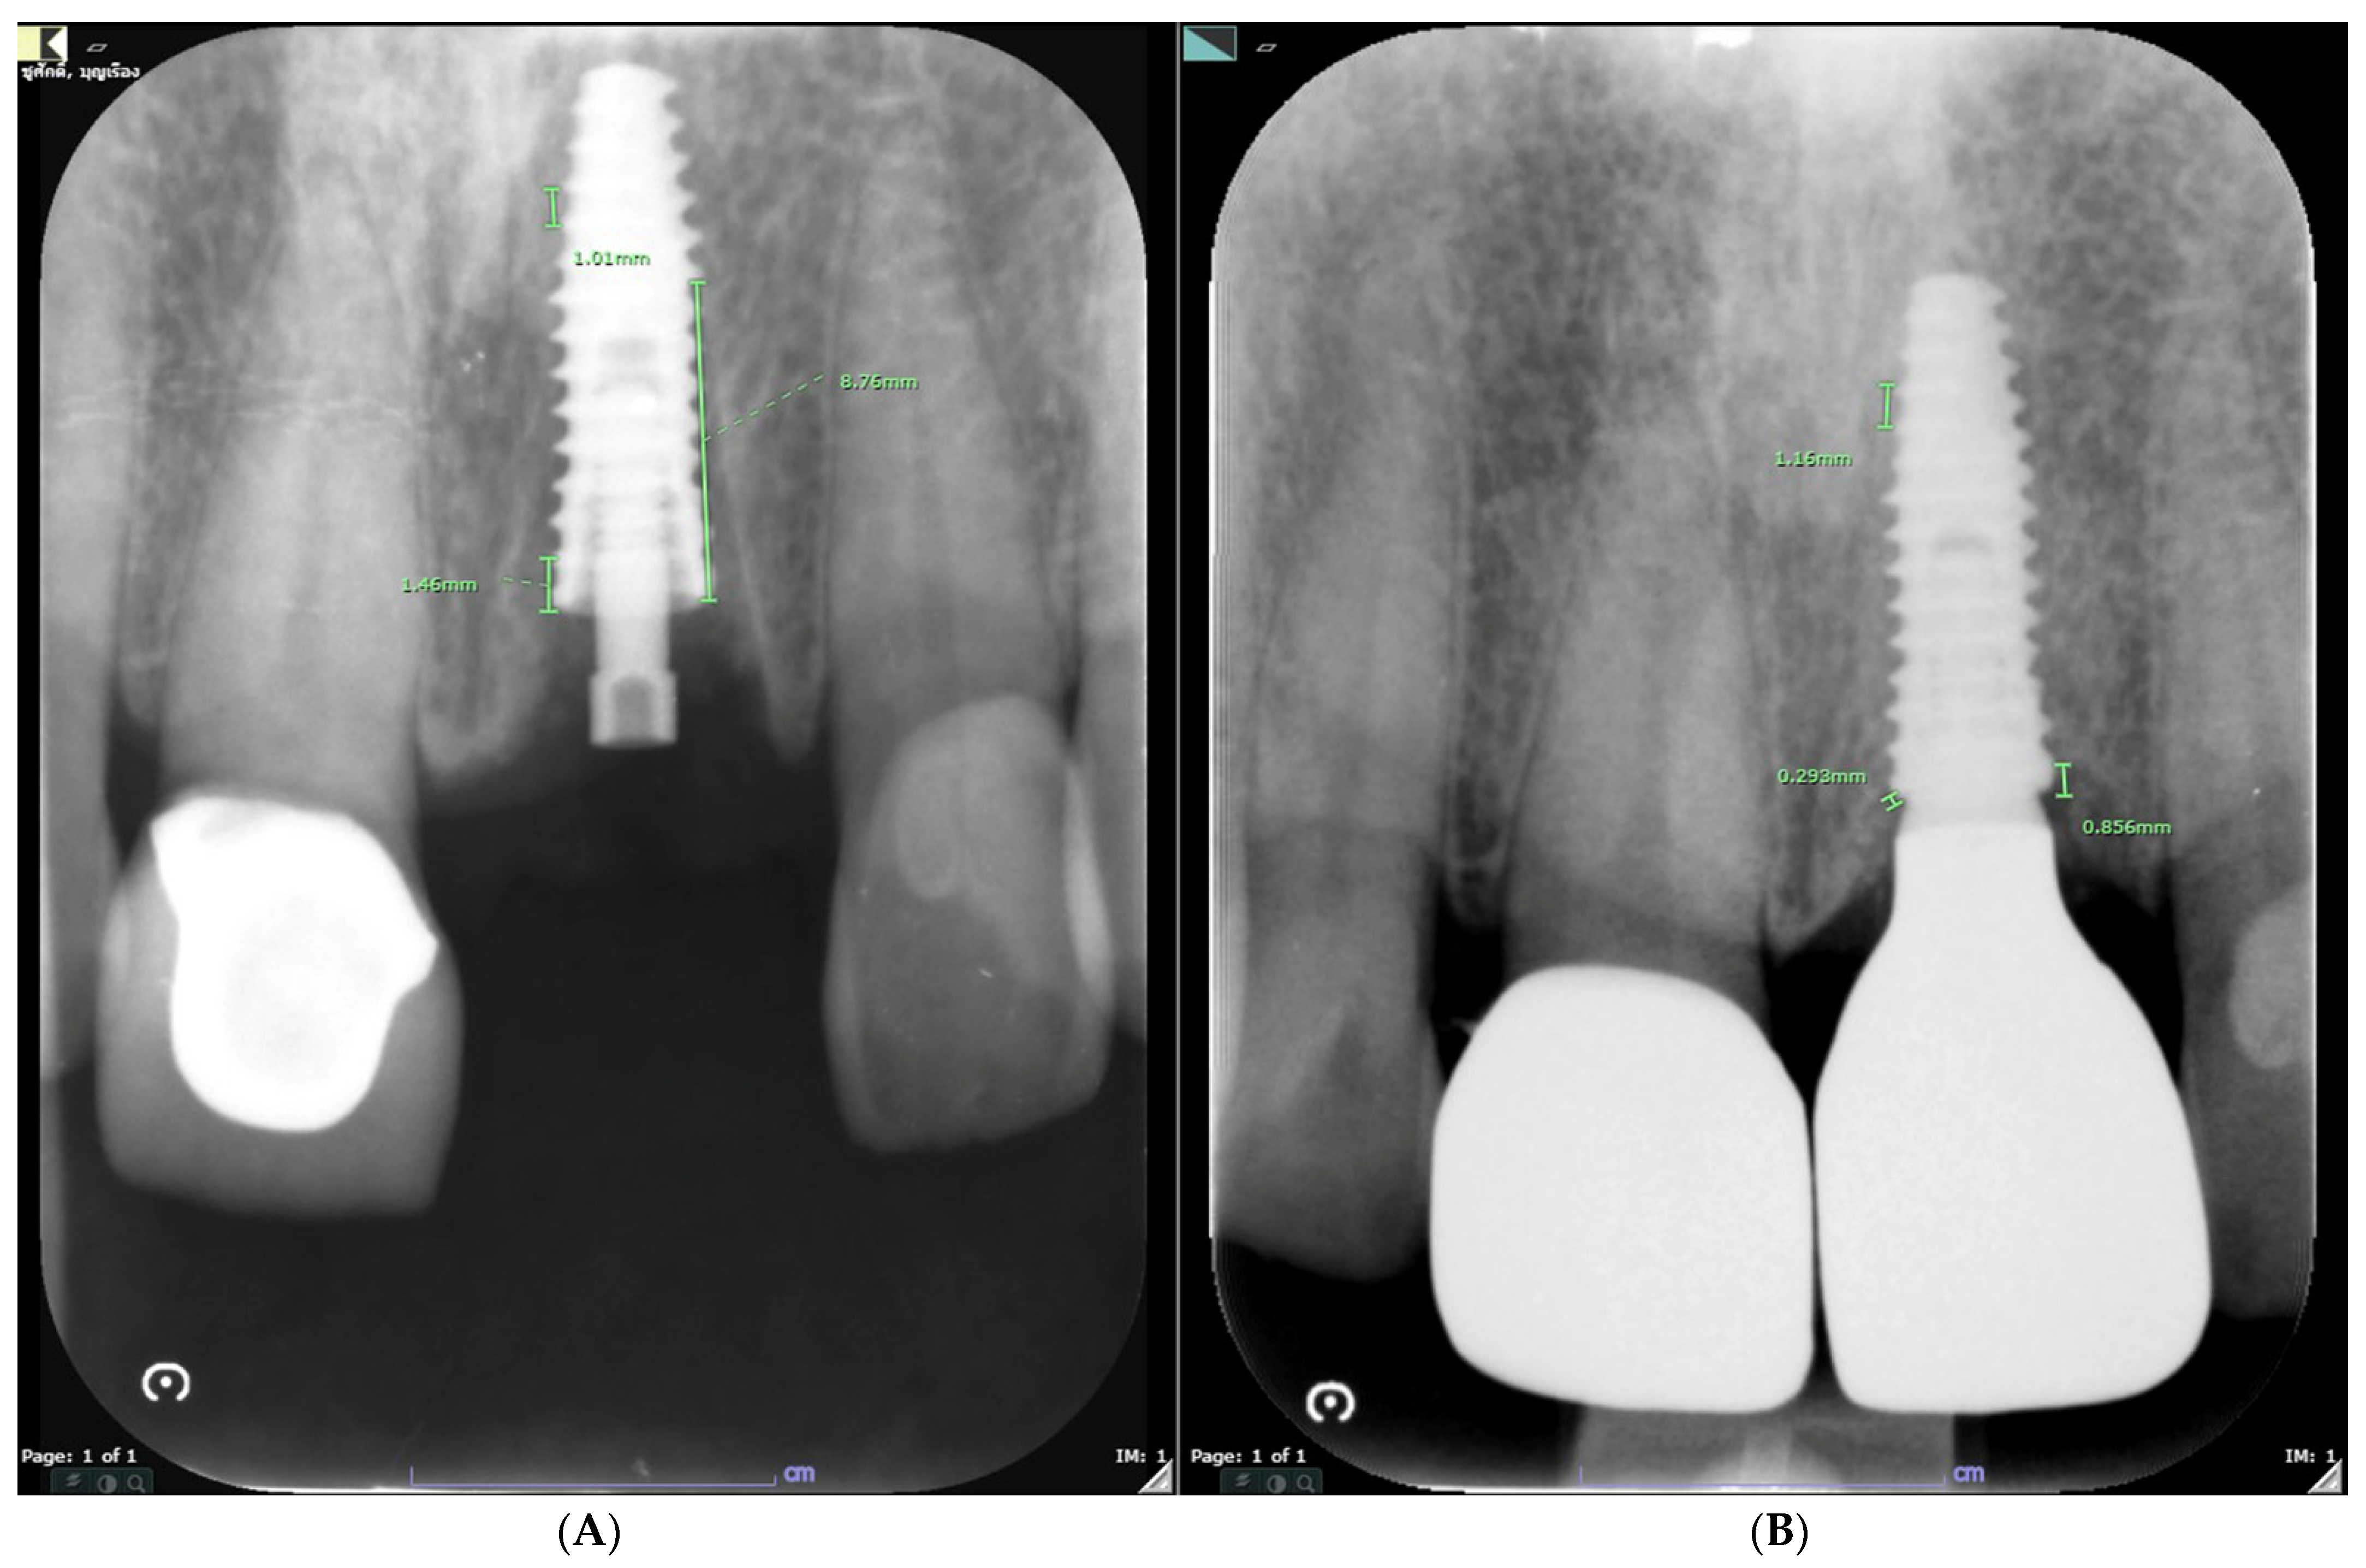

2.7. Case Presentation

3.2. Hard Tissue Parameters

Marginal Bone Change (mm); mBC and dBC